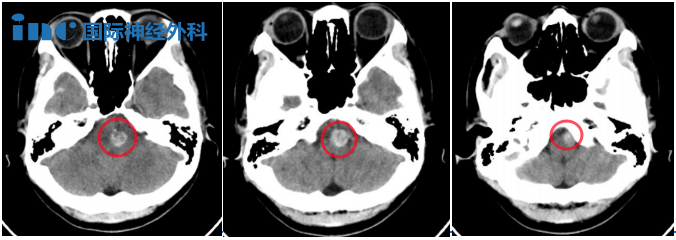

▼2023年11月头颅CT

原来,年仅28岁的琳琳2023年9月23日因复视、左眼外展受限、易疲惫、嗜睡等症状就诊上海某医院,完善头颅CT显示:脑干占位,微量出血可能,医生建议尽快做增强MRI,建议去上级医院就诊。随后就诊多家医院,查颅脑MRI平扫+增强提示:“延髓交界处,海绵状血管瘤可能”,考虑出血量较小,建议复查随访。然而,从2023年9月底至今,短短不到2个月时间,琳琳已经发生过2次脑干出血,复视、手脚发麻,症状一步步加重,但是医生给出的评估不是建议随访,就是手术风险较大。

2023年11月初,二次出血

症状:复视和右手脚掌麻,和之前一开始相比,眼部症状明显严重一些,易疲惫,嗜睡。

医生判断脑干海绵状瘤二次出血,对比一开始出血量增多。医生建议手术并告知术后可能出现偏瘫、呼吸障碍等神经功能损伤。